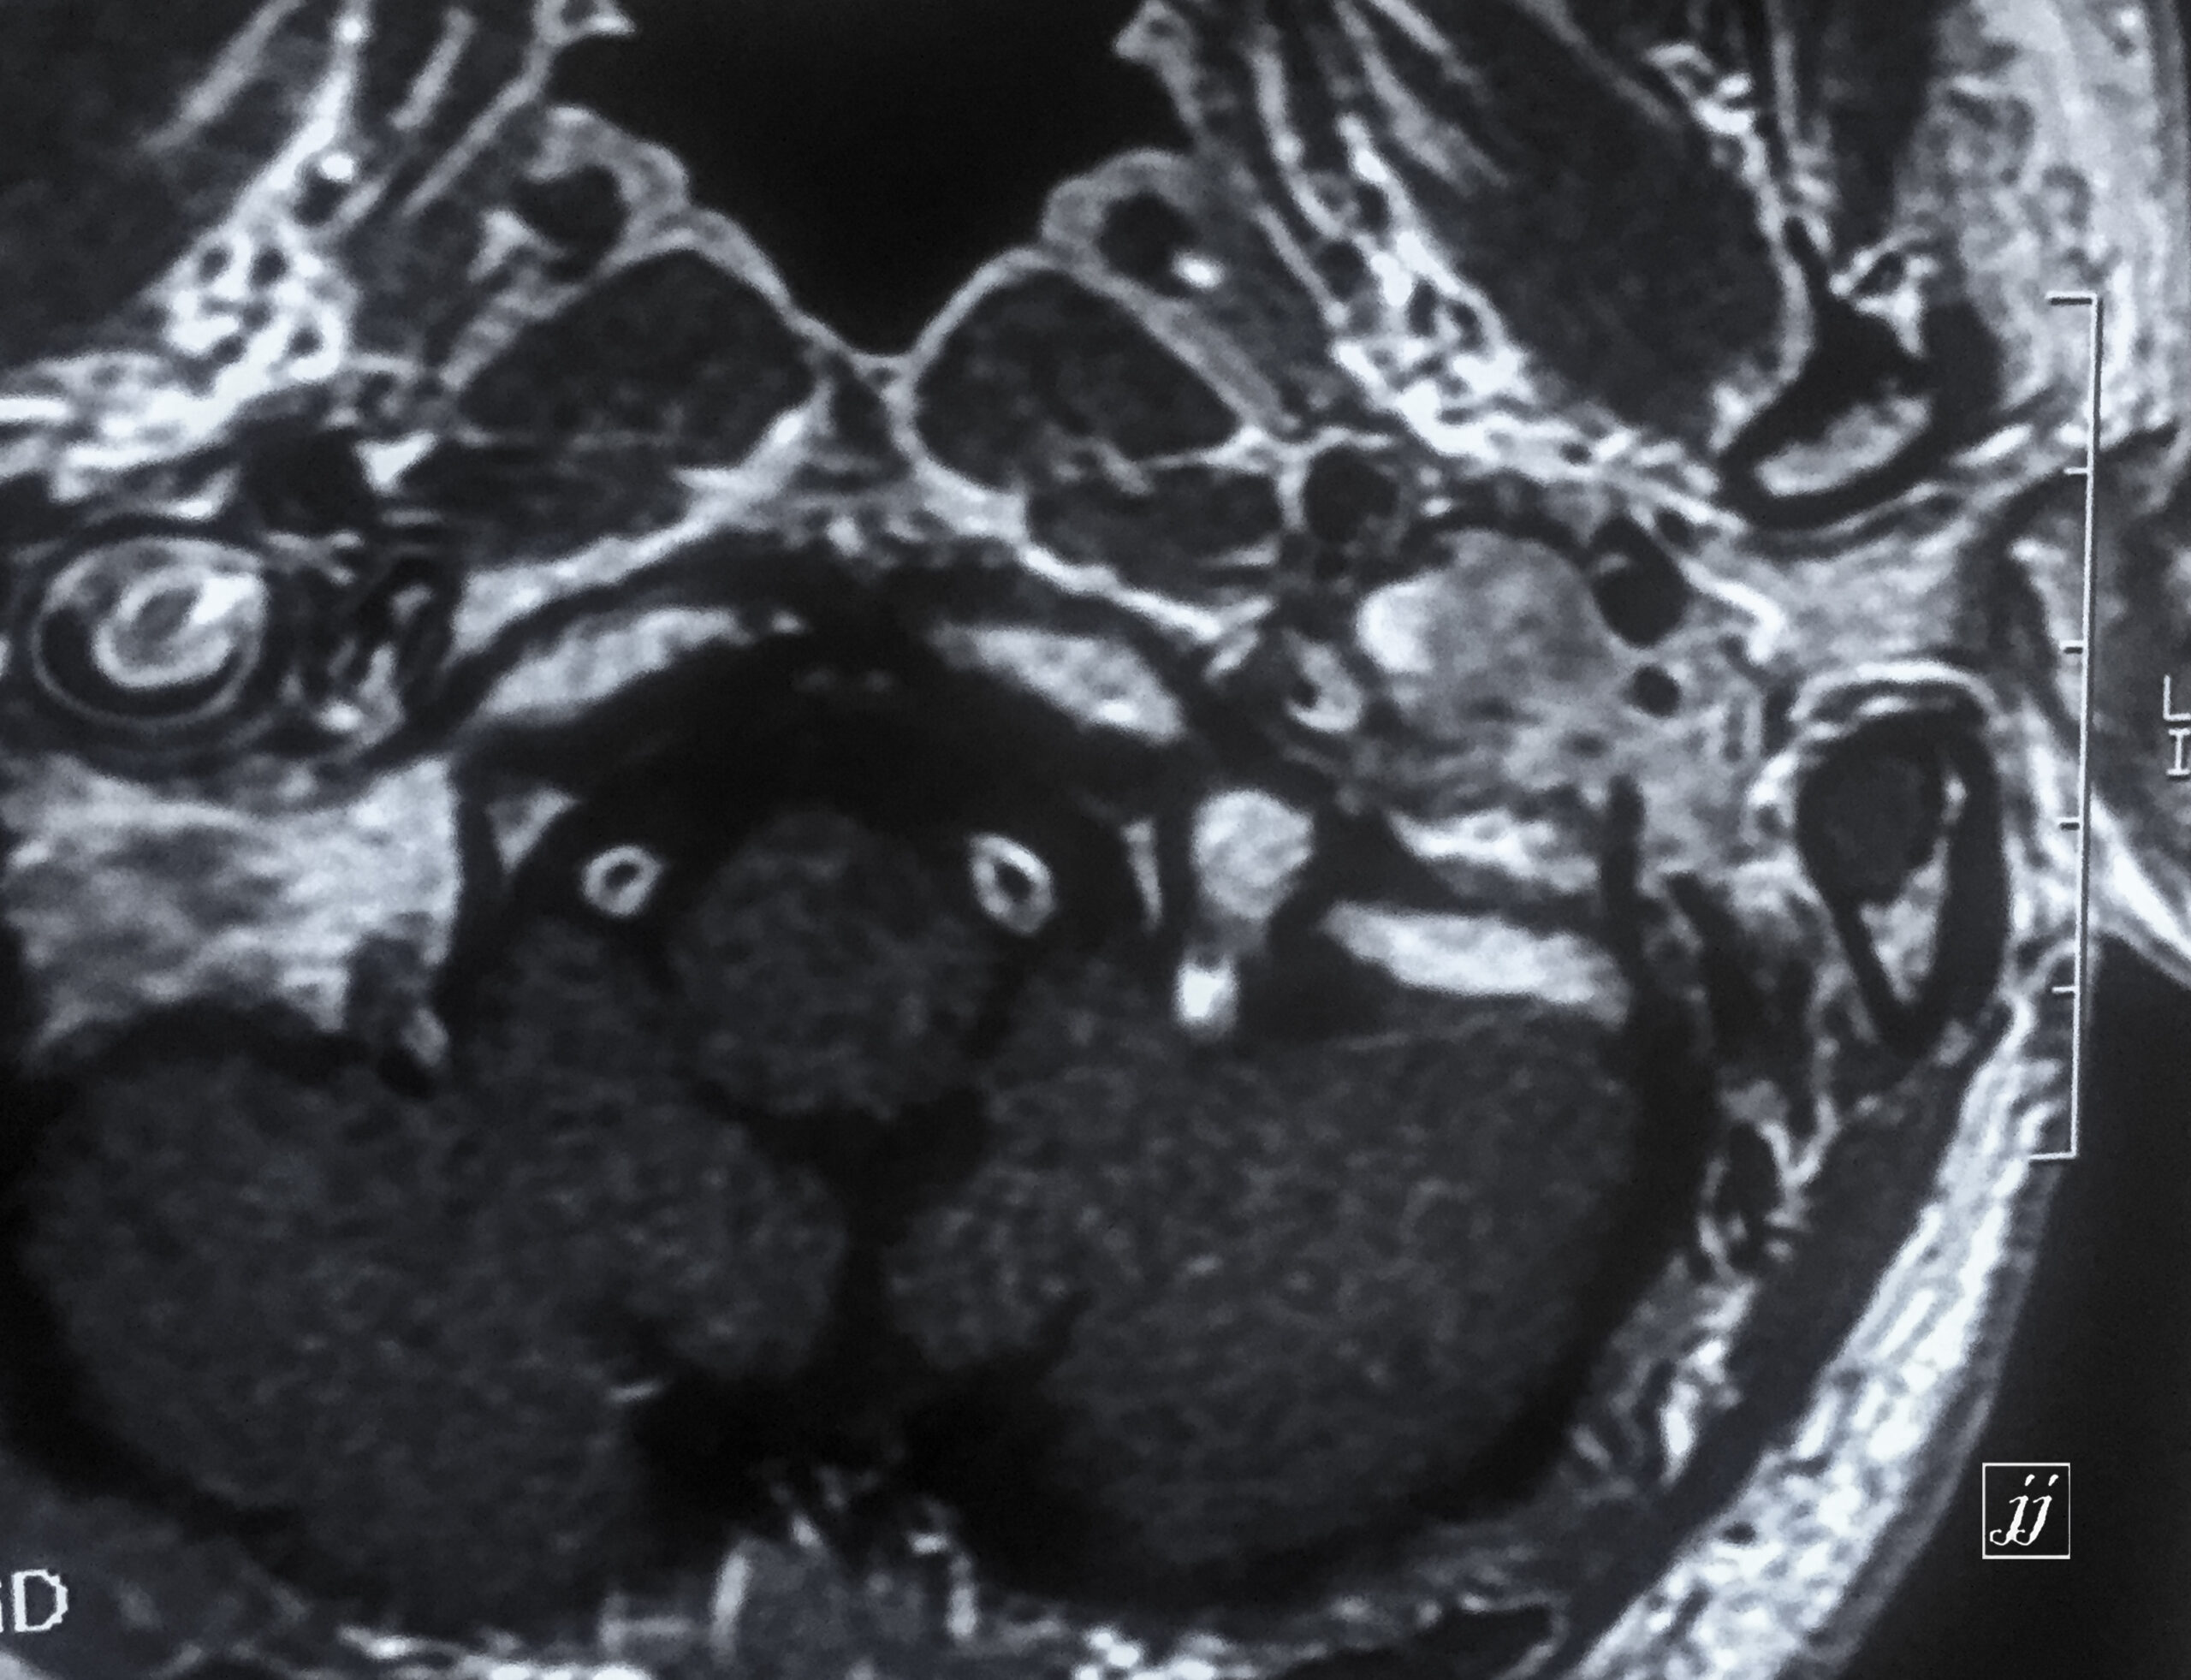

Brain- calcified vertebral arteries (3)